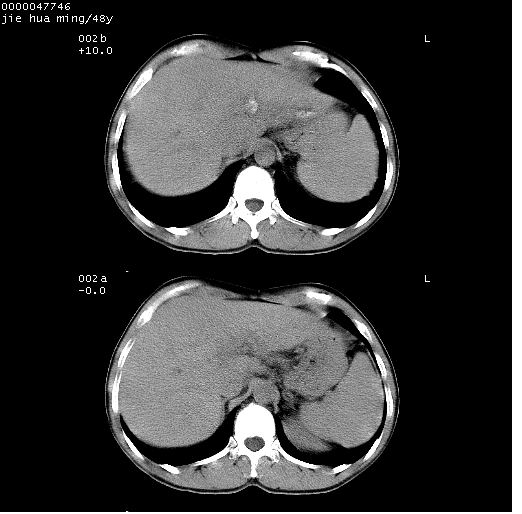

以下是引用dr.yang在2008-5-1 6:25:00的发言:[br]两肺广泛毛玻璃样的片状影,密度不均,边缘欠清,呈碎石路样改变,[br]考虑,1双肺间质性肺炎,2肺泡蛋白沉积症3支气管肺泡癌[br]

以下是引用hhcckk在2008-5-1 8:06:00的发言:[br]支持肺泡蛋白沉积症[br]依据:[br]1、病灶边缘清楚----地图征[br]2、病灶内部小叶间隔或小叶内间隔增厚所形成的网格状影----碎石路样表现[br]3、抗炎治疗无效(炎症抗炎治疗有效)[br]4、纵隔内未见肿大淋巴结(肺泡细胞癌时常有)[br][br]附肺泡蛋白沉积症资料[br][br]肺泡蛋白沉积症(pulmonary alveolar proteinosis)是一种原因不明的以肺泡腔内大量含脂糖蛋白样物质沉积为特征的疾病。[br]病理改变:(1)肺泡和细支气管腔内充满大量含脂糖蛋白样的粘稠物质,该物质为颗粒状或絮状的糖原pas染色阳性的磷脂蛋白。(2)肺泡壁及其间隔无异常改变。胸膜和淋巴结不受累及。(3)晚期可出现弥漫性肺间质纤维化。[br]临床表现:(1)好发年龄30~50岁,男性多于女性,偶见于儿童;(2)主要症状为呼吸困难、咳嗽、低热、消瘦、低氧血症和杵状指等。1/3的患者无症状。(3)实验室检查:痰液或肺泡灌洗液中可找到pas染色阳性颗粒物质。[br]hrct表现:肺泡蛋白沉积症具有特征性改变,即“碎石路样”表现(crazy-paving appearance,cpa)。主要包括(1)斑片状磨玻璃影:指肺野密度朦胧增加,内可见肺血管纹理影,系肺泡腔内充满低密度的磷脂蛋白物质所致。(2)其内部小叶间隔或小叶内间隔增厚所形成的网格状影,为小叶间隔水肿、肺泡壁内淋巴细胞和巨噬细胞浸润以及小叶内淋巴管扩张的缘故。(3)病灶边缘清楚,呈地图样分布于肺野外围或肺门及中央区。[br]

以下是引用zsl6918在2008-5-1 7:35:00的发言:[br]双肺磨玻璃样病变,可见铺碎路石征,病变区与正常区交错。边界清晰。符合肺泡蛋白质沉着征,高分辨扫描会更清楚漂亮。建议临床肺泡灌洗。

以下是引用yangyudong333在2008-5-1 5:36:00的发言:[br][br] 两肺广泛毛玻璃样的片状影,密度不均,边缘欠清,呈碎石路样改变,[br]考虑,1双肺间质性肺炎,2肺泡蛋白沉积症[br]